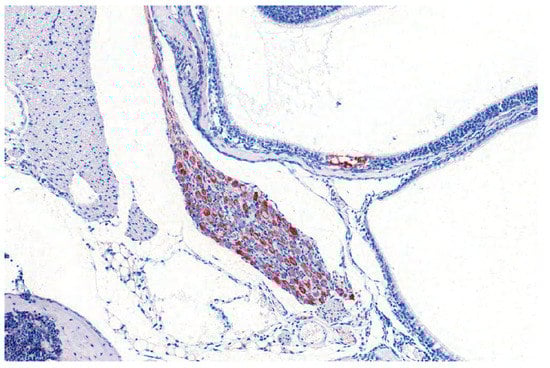

Rats and mice are less susceptible than rabbits. Compared to mice, rats display a greater resistance to PRV infection, since successful oral inoculation requires 106 PFU and mucosal injuries. In mice, 104 PFU is the minimal infectious dose, dependent on the virus strain [111]. Mice can be infected by various inoculation routes including: i.n., p.o., i.o., i.c., i.v., i.m., intraperitoneal (i.p.), s.c. or via foot pad [24,25,27,115,116,117,118,119,120,121]. Depending on the inoculation route, the incubation period of AD in mice is longest after intranasal or intraocular infection [115]. After intracerebral infection, mice are recumbent and comatose and die within two days post infection (p.i.). A generalized pruritus can be observed after intravenous and intraperitoneal inoculation with phases of frequent „face-washing“ [115]. With disease progression pruritus and edema at the head worsen, which is followed by collapse of the animals. Mice infected intranasally do not show skin lesions, but appear to be blind. They also show violent, spasmodic movements before they die. This is in contrast to previous experiments in mice, where intranasal infection leads to a more severe clinical picture [24,25,27,121]. Mice show hunching, anorexia, depression, hyperactivity and severe pruritus at the head (Figure 10). Some develop excitations, convulsions and dyspnea. The animals have hemorrhagic dermal erosions and ulcerations, nasal bridge edema and acute catarrhal conjunctivitis and do not survive longer than 3 d p.i. The same is true for subcutaneous (flank) inoculation in mice [118]. After intramuscular injection, mice exhibit intense pruritus at the inoculation site, collapse and die. Excessive itching, head edema and self-mutilation are also present in mice after intraocular infection [115]. Virus is only detectable in the brain after i.c. or i.o. infection. The spleen shows viral antigen positive cells after i.v. infection, whereas PRV can be found in the kidney after i.m., i.v. and i.p. and to some extent after i.n. infection [115]. In contrast, Klopfleisch et al. [25] did not identify viral antigen in other tissues than the brain and epithelial cells in the nasal mucosa after i.n. infection. Immunohistochemically, PRV antigen is localized in the respiratory and nasal gland epithelium, trigeminal ganglion, brainstem and to some extent in the midbrain. Further, the sympathetic superior cervical ganglion as well as the parasympathetic pterygopalatine ganglion are affected [24,25] (Figure 11). In addition, the olfactory epithelium, the vomeronasal organ as well as blood vessel walls are positive for viral antigen [121] as well as salivary glands [27]. Inflammation is only mild and occasionally present in the nose and superior cervical ganglion [27]. Subcutaneous inoculation results in infection of the brainstem and the cerebellum [118], whereas after foot pad inoculation virus can moreover be isolated from the sciatic nerve, lower spinal cord, adrenal gland, coeliac ganglia and paravertebral ganglia [119]. This is in line with inflammatory changes in dorsal root ganglia and at the site of inoculation [120].

Figure 11.

Pterygopalatine ganglion of a mouse infected experimentally with PRV. PRV-antigen reveals numerous positive neurons (red labelling by immunohistochemistry).